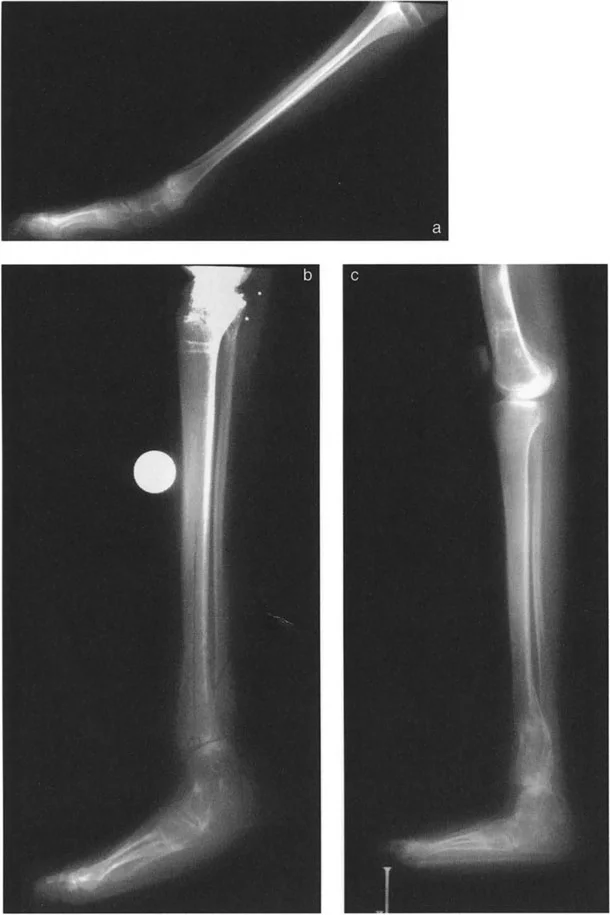

أنواع جراحات قطع العظم فوق الكاحل (Supramalleolar Osteotomy)

جراحة قطع العظم فوق الكاحل (SMO) هي الإجراء الأكثر شيوعًا لتصحيح تشوهات قصبة الساق البعيدة. تتضمن هذه الجراحة قطعًا دقيقًا في عظم الساق (القصبة) فوق مفصل الكاحل مباشرة، ثم إعادة محاذاة العظم وتثبيته في الوضع الصحيح. هناك عدة أنواع من هذه الجراحة:

1. قطع العظم الإسفيني الفاتح (Opening Wedge Osteotomy):

• يتم عمل قطع في العظم ثم فتح فجوة صغيرة فيه. تُملأ هذه الفجوة عادةً بترقيع عظمي (من جسم المريض أو من متبرع).

• المميزات: يحافظ على طول الطرف، وهو مفيد إذا كان المريض يعاني أيضًا من اختلاف في طول الساقين.

• العيوب: يتطلب ترقيعًا عظميًا، ويستغرق وقتًا أطول للالتئام، وقد يزيد من توتر الأنسجة الرخوة حول العظم.

2. قطع العظم الإسفيني المغلق (Closing Wedge Osteotomy):

• يتم إزالة قطعة صغيرة من العظم على شكل إسفين، ثم يتم تقريب أطراف العظم وربطها معًا.

• المميزات: يوفر استقرارًا عاليًا، ويسمح بالاتصال المباشر بين العظام، مما يسرع الالتئام ويسمح غالبًا بتحميل الوزن مبكرًا.

• العيوب: يؤدي إلى تقصير طفيف في الطرف، وهو ما قد لا يكون مرغوبًا في بعض الحالات.